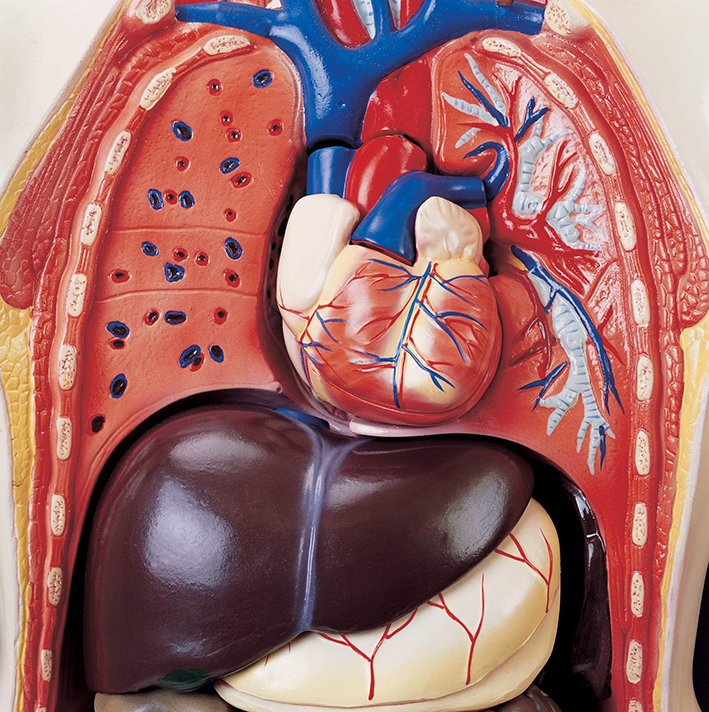

عکس اسکلت بدن انسان با کیفیت. عکس اسکلت عکس اسکلت برای پروفایل عکس اسکلت انسان عکس اسکلت خفن عکس اسکلت بدن انسان با کیفیت عکس اسکلت بدن انسان عکس اسکلت ترسناک عکس اسکلت فانتزی عکس اسکلت فانتزی دخترانه پرچم عکس اسکلت. عکس با کیفیت اسکلت داخلی انسان و درد و گرفتگی در ناحیه استخوان زانو ویژه استفاده در امور تبلیغاتی و تجاری طراحی کاتالوگ بروشور و تراکت با موضوع پزشکی فیزیوتراپی ارتوپد دکتر روماتیسم فیریوتراپ طب فیزیکی. عکس اسکلت بدن انسان زن و مرد آناتومی ساتین 16 سپتامبر 2017. اسکلت داربست بدن است تمام قسمت های بدن روی اسکلت قرارگرفته اند بدن انسان از ۲۰۶ قطعه استخوان تشکیل شده است این استخوان ها طوری با نظم کنار هم قرار گرفته اند که انسان را قادر می سازد حرکات دقیقی داشته باشد.

اسکلت جمجمه و گردن انسان ستون فقرات آناتومی اسکلت جمجمه و گردن انسان ستون فقرات آناتومی تصویر با کیفیت را از لینک زیر می توانید دانلود کنید. ۱ مطلب با کلمه ی کلیدی عکس اسکلت بدن انسان با کیفیت ثبت شده است گالری نسیم جدید ترین و با کیفیت ترین عکس های مناسبتی. عکس با کیفیت آناتومی اسکلت بدن انسان و درد و دیسک در قسمت مهره های ستون فقرات کمر ویژه استفاده در امور تبلیغاتی و تجاری طراحی کاتالوگ بروشور و تراکت با موضوع بیمارستان ها و کلینیک ها و درمانگاه ها و مطب ها پزشکان و.